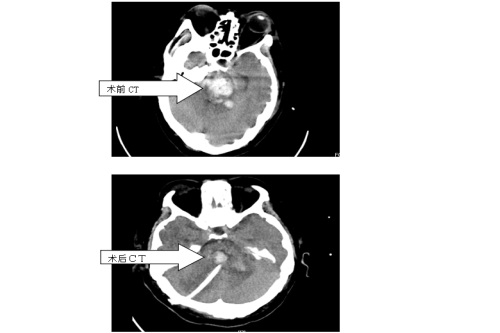

近日,临床医学院/附属医院神经外科成功为一例脑干出血患者行九江地区自主进行的首例“立体定向下脑干出血穿刺外引流术”,手术顺利,置管成功,术后引流效果佳。

患者入院时呈神志深昏迷状态,GCS4分,CT提示脑干出血。脑干出血是脑出血中最凶险的一种,一直被认为是手术禁区,患者死亡率及致残率极高,以前传统治疗均为给予药物保守治疗。近年来有些大医院开展开颅手术清除血肿,但并不能改善患者预后,没有得到广泛推广。经过与患者家属充分沟通,神经外科赵浪平主任医师带领张国斌副主任医师,周嘉敏、黄启伟主治医师,朱鹏博医师等一起为患者行“脑干出血立体定向下穿刺外引流术”。该手术具有恢复快、住院时间短、治疗费用低等优点,是一种创伤小、治疗确切、家属容易接受的治疗手段。

临床医学院/附属医院自引进新的立体定向仪以来,就已开展了多例“脑出血”的“立体定向脑内血肿置管外引流术”,均取得了成功。立体定向仪不但可以行脑出血“靶向”治疗,对于颅内微小病变及无法明确诊断的病变也可进行“靶向”下活检,还可以立体定向下脑内放疗置入、脑内深部电刺激、脑内深部电极置入、帕金森病的毁损和电极置入等治疗,它具有创伤小、定位准确、费用低的优点。此次该院神经外科进行的“脑干出血立体定向下穿刺外引流术”为九江地区自主进行的第一例该种手术,标志该院神经外科又向前迈出了坚实的一步。